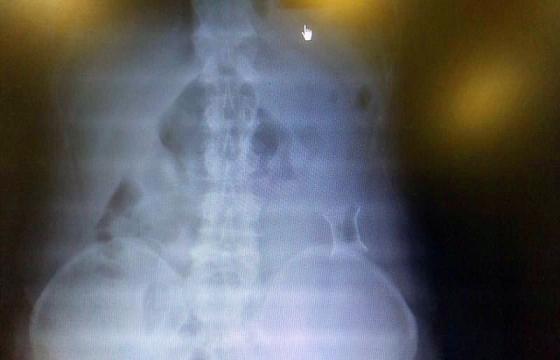

受試患者在結(jié)腸端端吻合術(shù)中,使用我司新研制產(chǎn)品達(dá)到了理想的預(yù)期效果。患者術(shù)后7天、14天X光片顯影,可降解腸道支架均能按研制設(shè)計(jì)的預(yù)期時(shí)間節(jié)點(diǎn)保持應(yīng)有強(qiáng)度,術(shù)后21天X光片顯示可降解腸道支架已完全破碎,并排出體外。在整個(gè)試驗(yàn)過(guò)程中,病患無(wú)任何不良反映,耐受良好。